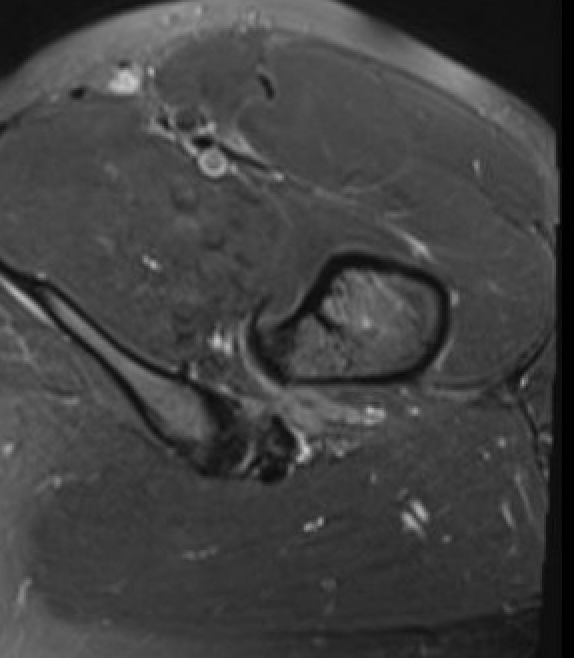

MRI

Reduced ischiofemoral space - distance between the lesser trochanter and the ischial tuberosity

Reduced quadratus femoris space - distance between hamstring tendon and iliopsoas

Inflammation / edema in quadratus femoris +/- fatty degeneration

Singer et al Skeletal Radiol 2015

- systematic review of 190 hip MRI of patients with ischiofemoral impingement

- compared to controls

- ischiofemoral space < 15 mm: sensitivity  77%, specificity 81%, accuracy 78%

- ischiofemoral space < 10 mm: sensitivity 79%, specificity 74%, accuracy 77%.